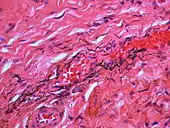

Silver sulfide deposits in the surrounding area of skeletal muscle fibers of the oral mucosa

If necessary, the diagnosis can be confirmed histologically by excisional biopsy, which excludes nevi and melanomas.[3]:138 If a biopsy is taken, the histopathologic appearance is:[1]

• Pigmented fragments of metal within connective tissue

• Staining of reticulin fibers with silver salts

• A scattered arrangement of large, dark, solid fragments or a fine, black or dark brown granules

• Large particles may be surrounded by chronically inflamed fibrous tissue

• Smaller particles surrounded by more significant inflammation, which may be granulomatous or a mixture of lymphocytes and plasma cells